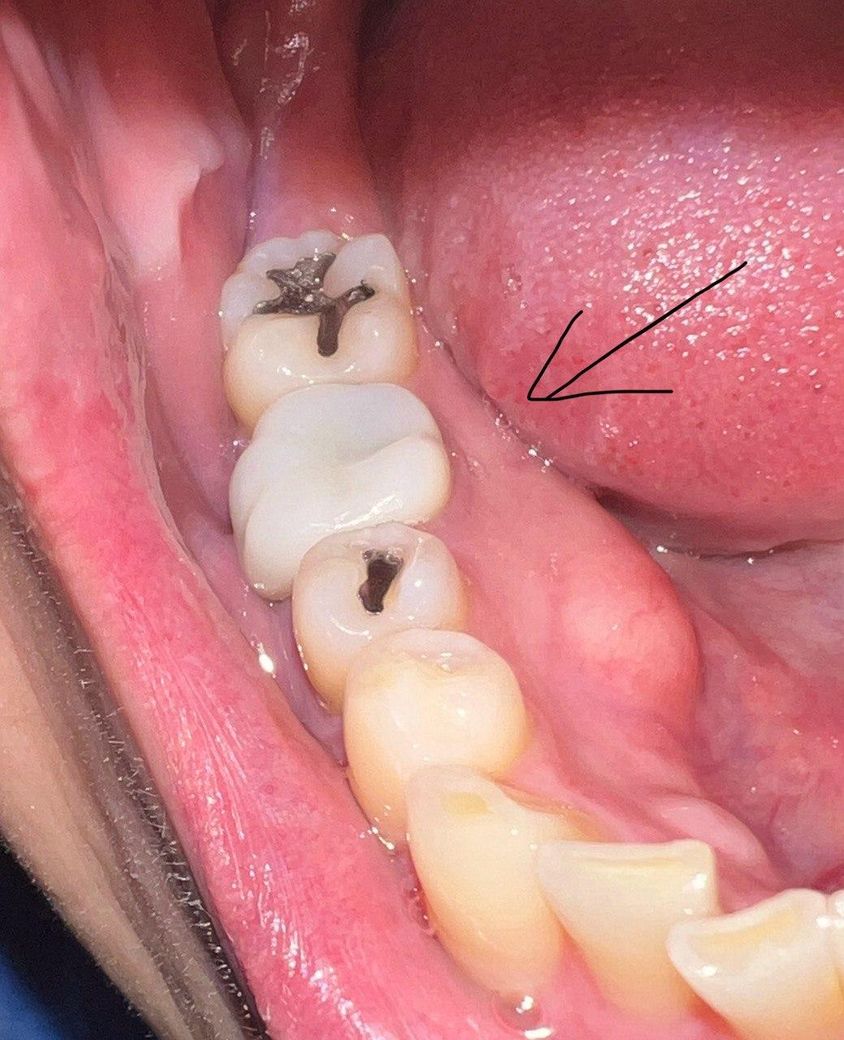

약 5년전 어금니에 크라운을 씌웠는데

오늘 우연히 거울을 보니 아래 사진처럼 잇몸이 살짝 녹아서(?) 내부 치아가 드러나있는걸 발견했습니다.

다행히 시리거나, 통증이 있거나, 크라운이 흔들리거나, 피가 나는 등의 문제는 없습니다.

보철치료를 하고 난다음 경계부위가 내려가면서 보철물의 경계가 보일수 있습니다. 크게 문제가 되지는 않지만 심미적으로 신경이 쓰인다면 보철치료를 다시 받는 것이 좋을수 있습니다.

나이가 들면서 잇몸이 퇴축되면서 치아의 뿌리가 약간 노출된거 같습니다. 일단은 관리를 하시면서 사용하셔도 될것같습니다.

간혹 시간이 지남에 따라 저렇게 잇몸이 내려가긴 하지만 주위 잇몸 상태가 건강한 것으로 보아 병적인 상태는 아니니 걱정하지 않으셔도 되겠습니다.